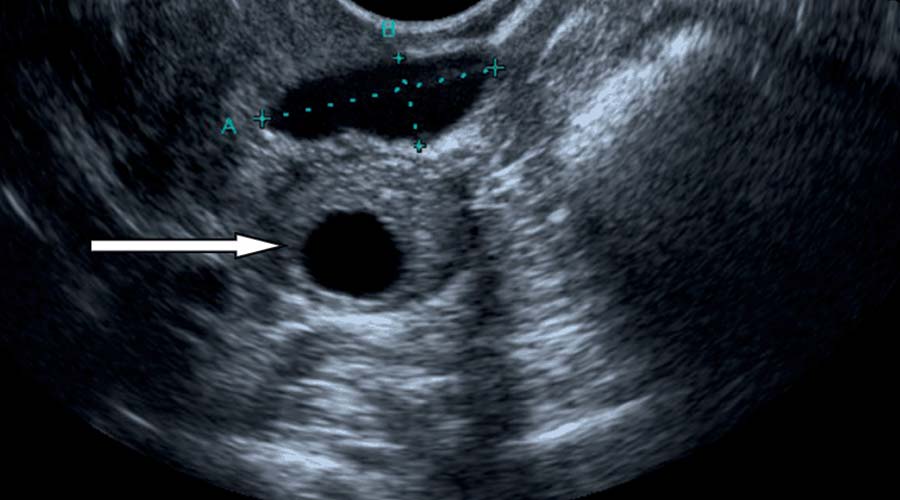

کیست تخمدان چیست؟

کیست تخمدان ساختارهایی بسته و کیسهمانند درون تخمدان دارد که حاوی یک ماده مایع یا نیمه جامد است. “کیست” صرفاً یک اصطلاح کلی برای یک ساختار پر از مایع است که ممکن است تومور یا نئوپلاسم را نشان دهد یا نباشد (رشد جدید). اگر تومور باشد، ممکن است خوش خیم یا بدخیم باشد.